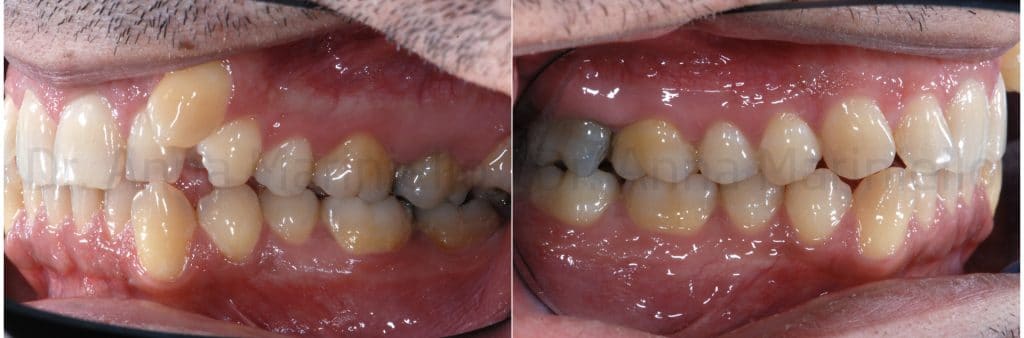

The following photos were taken at the end of distalization from 24 to 26 and alignment: